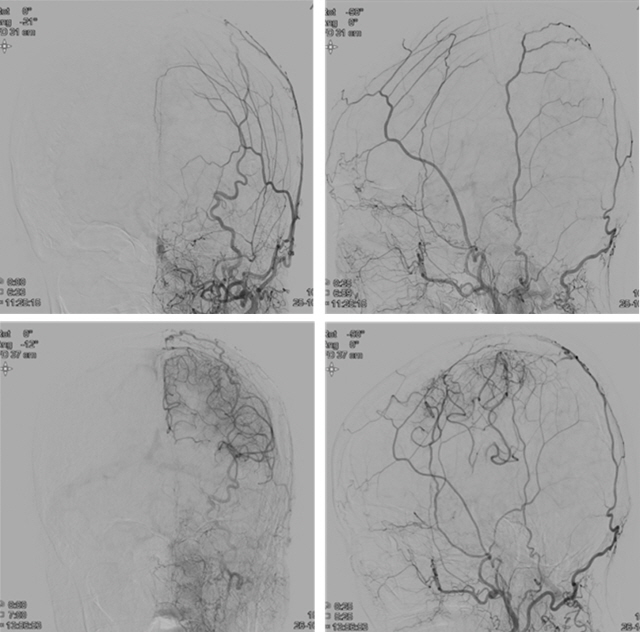

치료전(왼쪽)과 치료후의 모습. 새로운 치료법 적용 후 정상적인 혈류를 보이고 있다./사진=아주대병원 제공

국내 연구진이 막힌 뇌혈관을 뚫기 어려울 때 새로운 혈관을 생성해 혈류를 회복하는 치료법을 개발한 뒤 그 효과를 입증했다.

아주대병원 뇌졸중팀(신경과 홍지만·이진수·이성준, 신경외과 임용철 교수)은 뇌경색 환자에게 새로운 혈관을 생성해 감소한 혈류를 회복시키는 치료법을 개발했다. 치료법은 크게 2단계로 나뉜다. 1단계는 새로운 혈관이 잘 생기도록 하는 약물 투여고, 2단계는 국소마취 하에 두개골(머릿뼈)에 작은 구멍을 뚫는 병합치료다. <사진2>과 같이 두개골을 사이에 두고 바깥쪽에 위치한 좋은(혈류가 풍부하고 건강한) 혈관이 뚫린 구멍을 통과해 두개골 안쪽으로 뻗어나가 점차 뇌혈류가 안정적으로 흐르게 된다.

연구진은 2016년 7월부터 2019년 7월까지 막힌 뇌혈관을 뚫기 힘든 급성기(증상발생 2주 이내) 혈관 폐쇄성 뇌졸중 환자 42명(모야모야병 11명, 만성 동맥경화성 혈관 폐쇄 31명)에게 새로운 치료법을 적용했다. 연구팀은 환자들을 부분마취로 구멍만 뚫은 환자군(21명)과 약물과 구멍을 뚫는 병합치료 환자군(21명) 2개 그룹으로 나뉘어 분석했다.

그 결과 구멍 단독군에선 21명 중 12명(57.1%)이, 병합 치료군에선 21명중 19명(90.5%)이 수술에 성공했다. 혈관재형성 비율의 경우 구멍 단독군은 총 58개 구멍 중 30개(51.7%), 병합치료군은 총 58개 구멍 중 42개(72.4%) 구멍에서 혈관이 재생돼 병합치료군이 구멍 단독군에 비해 치료 성적이 더 큰 것을 확인했다.